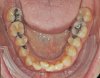

Das Quietschen fällt mir schon gar nicht mehr auf. Aber ich trage sie weiterhin fleißig. Ich kann schon sagen, dass sich der Zahn, gut eingestellt hat. Vor vier Monaten konnte ich noch die Kaufläche mit meiner Zunge beim zubeißen erfühlen. Das geht jetzt nicht mehr. Ich schaue mal, ob ich gleich noch die Fotos meiner KFO vor der Behandlung und von vier Wochen hochladen kann. Da kann man den Unterschied schon gut erkennen. Was ich als Laie halt so sagen kann. Außerdem habe ich das Gefühl, dass mein rechter vorderer Eckzahn etwas mehr Platz hat und nicht mehr so weit nach vorne steht.

Okklusion_rechts-Anfangsdiagnostik-2023_09_20-0_2[1].jpg Okklusion_Anterior-Anfangsdiagnostik-2023_09_20-0_1[2].jpg Okklusion_links-Anfangsdiagnostik-2023_09_20-0_3[1].jpg Okklusion_OK-Anfangsdiagnostik-2023_09_20-0_4[1].jpg Okklusion_UK-Anfangsdiagnostik-2023_09_20-0_5[1].jpg DSC_7646[1].JPG DSC_7649[1].JPG DSC_7651[1].JPG DSC_7652[1].JPG DSC_7655[1].JPG

Ich hoffe, ihr könnt auf diesen Bildern die Entwicklung sehen.